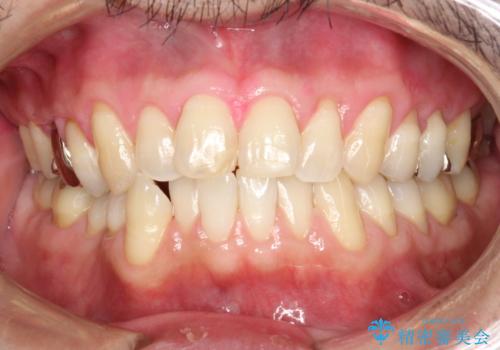

- 歯科でのクリーニングがかなり久しぶりで口臭も気になるとのことで来院されました。PMTCの60分コースで、染め出し・ブラッシング指導・クリーニングを行いました。

口臭は、様々なことからの原因がありますが、お口の中の細菌が繁殖することにより発生するともいわれています。多くの場合は正しい歯磨きを習慣づけることで、減少されます。毎日のご自身でのケアと、定期的に歯科医院にてPMTCを受けることにより、息をさわやかにすることができます。

磨けているよう、磨いているつもりでも、汚れが残ってしまうと、毎日の歯磨き時間が無駄になってしまうこともあります。効率的に歯磨きを行い、磨き残しを減らせるように、歯科衛生士による専門的な指導を行います。